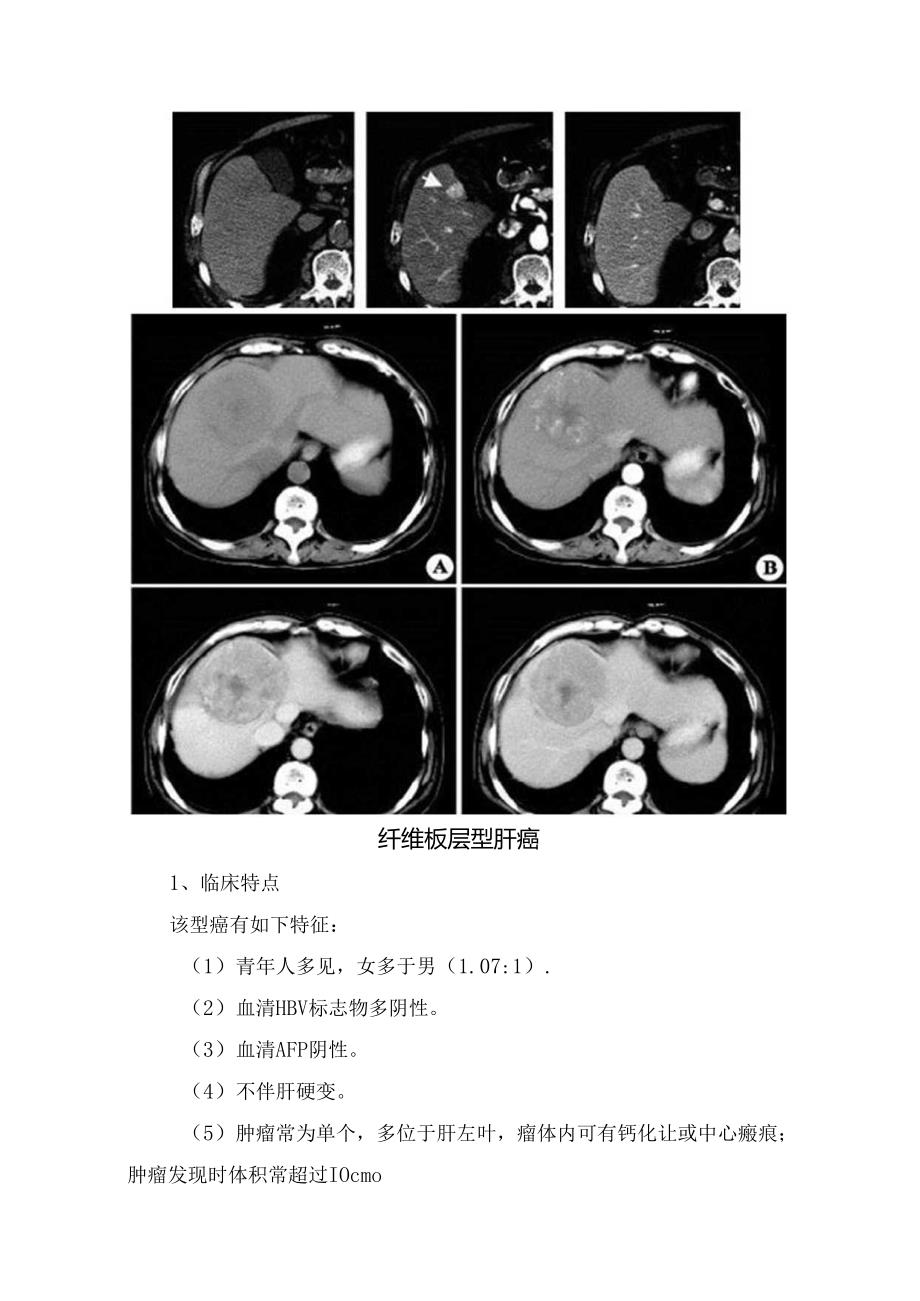

3、度。4、延时扫描为低密度。纤维板层型肝癌1、临床特点该型癌有如下特征:(1)青年人多见,女多于男(1.07:1).(2)血清HBV标志物多阴性。(3)血清AFP阴性。(4)不伴肝硬变。(5)肿瘤常为单个,多位于肝左叶,瘤体内可有钙化让或中心瘢痕;肿瘤发现时体积常超过IOcmo(6)分化程度好,生长缓慢。(7)切除后生存期长,平均32飞8个月。该型肝癌在我国少见,在肝癌低发的某些西方国家多见。2、病理特点肿瘤大多为单个实性结节,以癌细胞巢间出现大量平行排列的板层状纤维组织及强嗜酸性颗粒状的癌细胞浆为其主要病理特点。癌细胞索被平行的板层状排列的胶质纤维隔开,因而称为纤维板层型肝细胞癌。3、CT影像

4、表现呈巨块型,边缘可有分叶,CT平扫呈等或低密度灶,分界清楚,可有包膜,中央有星状更低密度纤维蔽痕向周围放射。动脉期肿块明显强化,门静脉期肿块强化消退,中央瘢痕在动脉期及门脉期无明显强化,可见斑点状钙化。极少伴门静脉瘤栓形成。FNH中央疤痕有延迟强化,而F1.C的疤痕无强化。肝血管瘤肝血管痛在组织学上分为海绵状血管瘤、硬化性血管病、血管内皮细胞瘤和毛细血管瘤。是肝脏最常见的良性肿瘤。肝脏的血管瘤多数为海绵状血管痛。多无临床症状。1、病理表现单发或多发,可位于肝包膜卜.,向外突出于肝表面,也可比较深在。肿瘤被覆结缔组织被膜,与周围肝组织分界清楚,由充满血液的血管囊腔构成,囊腔间有纤维性分隔。肿病